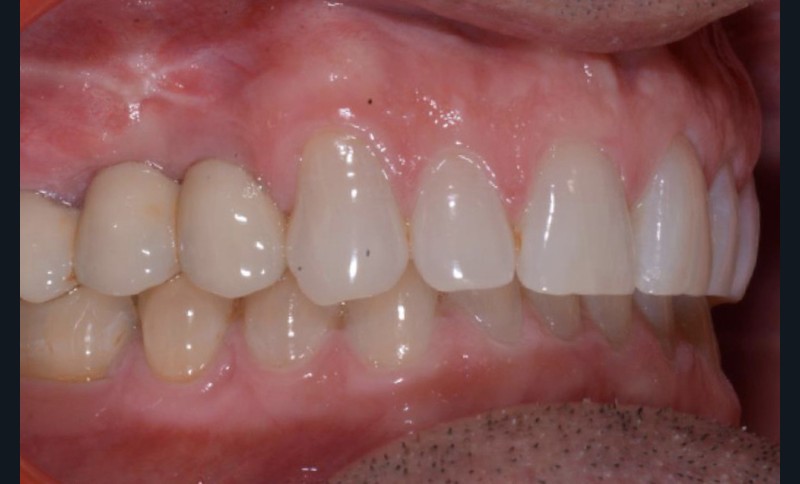

Conclusion

Les techniques orthodontiques de déplacement par gouttières orthodontiques thermoformées sont très efficaces pour gérer des situations simples. Ce patient en montre l’intérêt, en particulier lorsque la forme d’arcade dentaire doit être maintenue. Les systèmes « in-office » peuvent tout à fait permettre la gestion de ces situations.